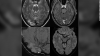

脳の中に幼虫が寄生、長年続いた頭痛の原因 豪女性 |